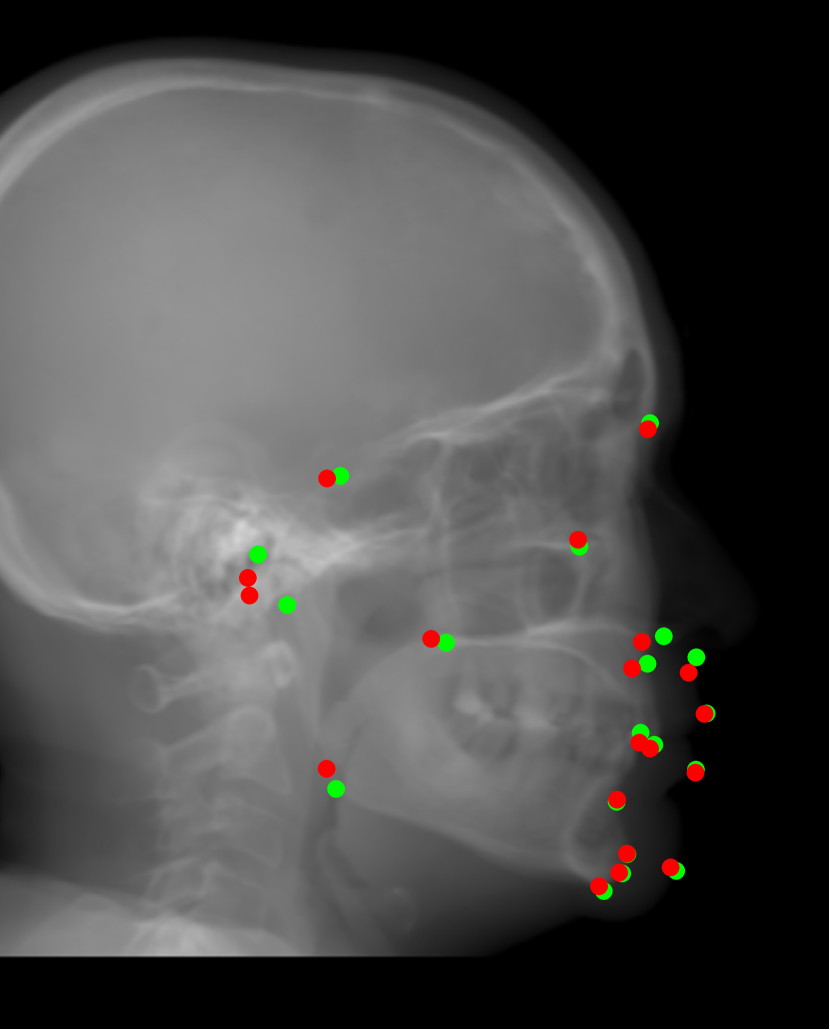

Refer to caption

Fig. 1: A graphical abstract of our contributions to cephalometric analysis in dental CBCT systems.

In order to address the above mentioned aspects in cephalometric analysis, the following contributions, displayed in Fig. 1 as an overview, are made in this work:

1. Image contrast: a nonlinear sigmoid-based intensity transform according to the optical property of X-ray films is proposed for Type I cephalogram synthesis;

2. Low dose: direct cephalogram synthesis from dual CBCT projections is proposed, where the advantage of using dual projections over one projection, the selection of patches, and the feasibility of one model for multi-quadrant patches are elaborated;

3. Image resolution: super resolution (SR) techniques using different adversarial generative networks (GANs) are investigated;

4. Landmark detection: an efficient automatic landmark detection method is proposed, which is applicable to real and synthetic cephalograms.